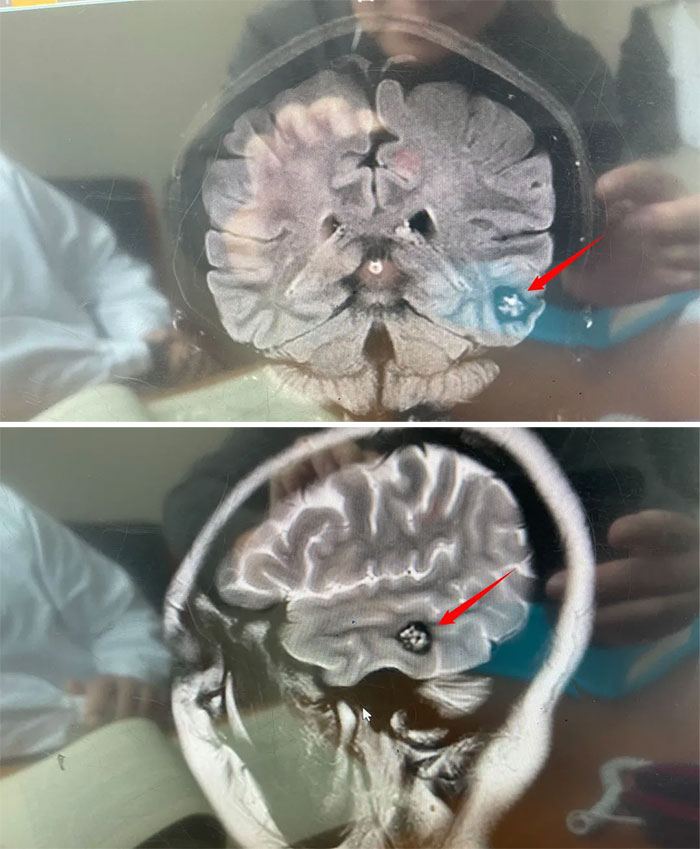

近期,头痛进行性加重,林女士去当地医院就诊,MRI检查提示:左侧颞叶凸面异常信号结节灶,提示海绵状血管瘤可能性大,建议手术。经慎重选择,以及亲友推荐,林女士来到了上海蓝十字脑科医院。

医院神经外科6A病区侯增欣主任团队为林女士完善相关检查,头颅磁共振显示:左侧颞叶见类圆形局灶性异常信号灶,约1.5*1.7*1.2cm。灶心“蜂窝状”,灶内微量出血(亚急性期)。

▲病灶灶心呈“蜂窝状”